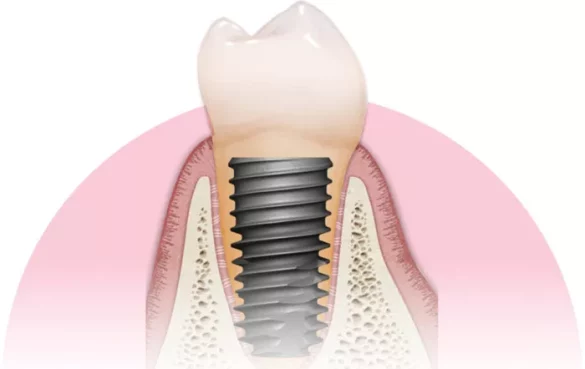

Strong Primary Stability: Their tapered body and aggressive thread design provide excellent initial stability, crucial for successful osseointegration and long-term success.

Advanced Surface Technology: Hiossen uses a sandblasted and acid-etched (SA) surface combined with a unique nano-hydrophilic coating that accelerates bone healing and integration, even in patients with poor bone quality.

Biocompatible Materials: Made from highly pure titanium alloy, Hiossen implants are corrosion-resistant and cause minimal allergic reactions, reducing the risk of complications.

Hiossen implants are made from highly pure titanium alloy, which is corrosion-resistant and biocompatible. This material choice minimizes allergic reactions and promotes better integration with the jawbone. The surface treatments—such as sandblasting, acid etching, and nano-hydrophilic coatings—enhance the implant’s ability to bond with bone tissue, facilitating faster healing and long-lasting stability.

Enhanced Osseointegration: Thanks to their advanced surface treatments, these implants integrate quickly and securely with bone, reducing healing time by over 20% compared to traditional implants.

Strong Mechanical Stability: The implant design, including a deeper implant-abutment connection and increased wall thickness, reduces the risk of screw loosening and fractures.